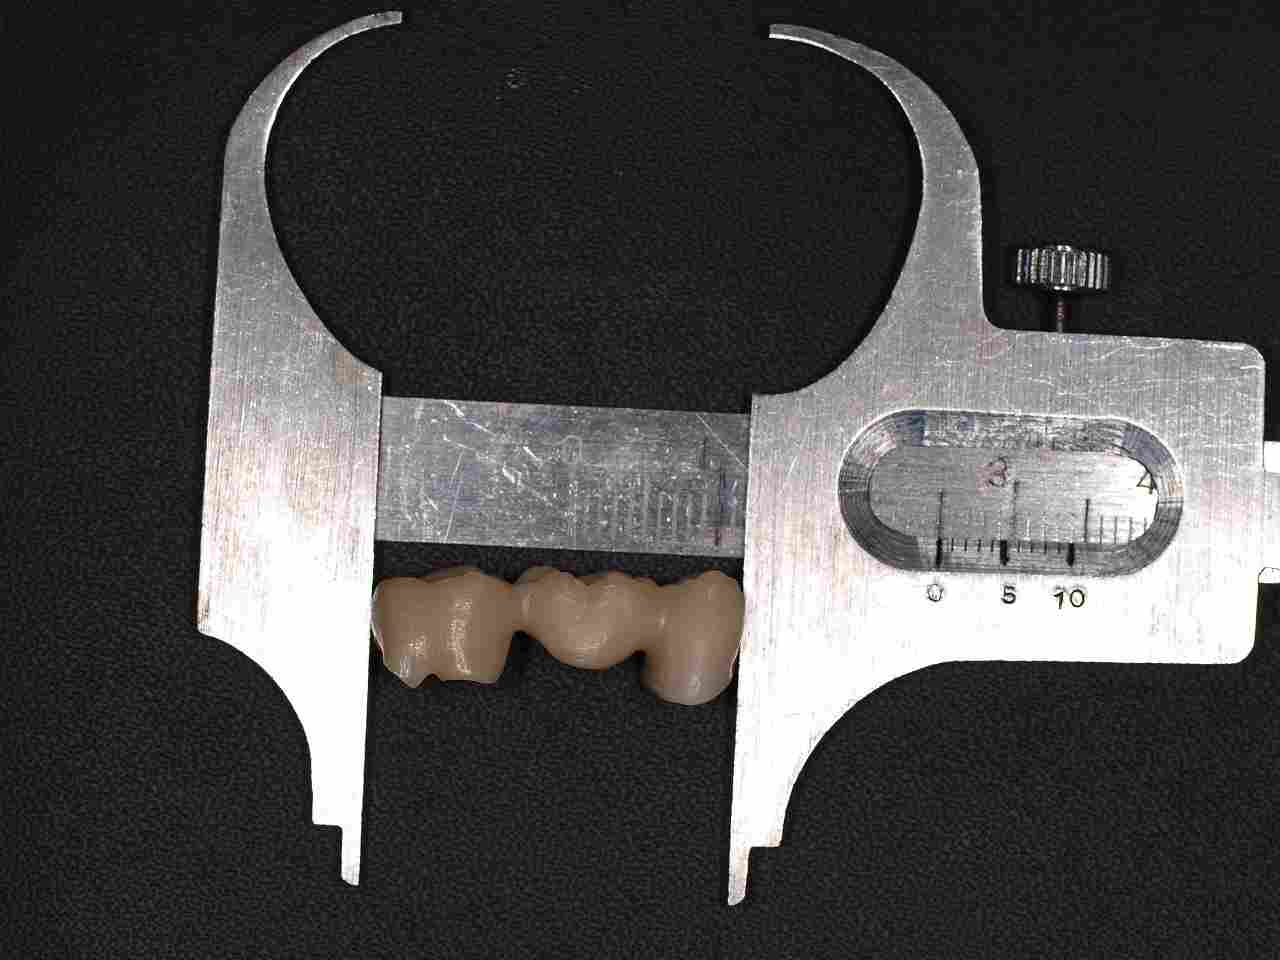

ジルコニアフレームを使用したジルコニアブリッジも6歯程度まででそれ以上になると従来通りのメタルボンドに切り替えるようにしています。 ワンピースではフレイムの適合、制度が落ちる為郎着作業が必要となりジルコニアは蝋着ができないことが理由に挙げられます。|お知らせ |広島市安佐南区の歯科医院

ジルコニアフレームを使用したジルコニアブリッジも6歯程度まででそれ以上になると従来通りのメタルボンドに切り替えるようにしています。 ワンピースではフレイムの適合、制度が落ちる為郎着作業が必要となりジルコニアは蝋着ができないことが理由に挙げられます。

ジルコニアフレームを使用したジルコニアブリッジも6歯程度まででそれ以上になると従来通りのメタルボンドに切り替えるようにしています。 ワンピースではフレイムの適合、制度が落ちる為郎着作業が必要となりジルコニアは蝋着ができないことが理由に挙げられます。